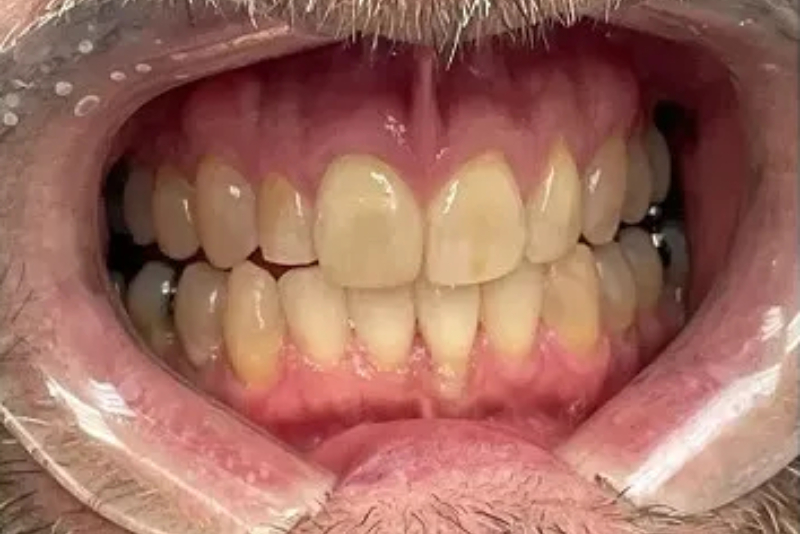

Before

After

Invisalign